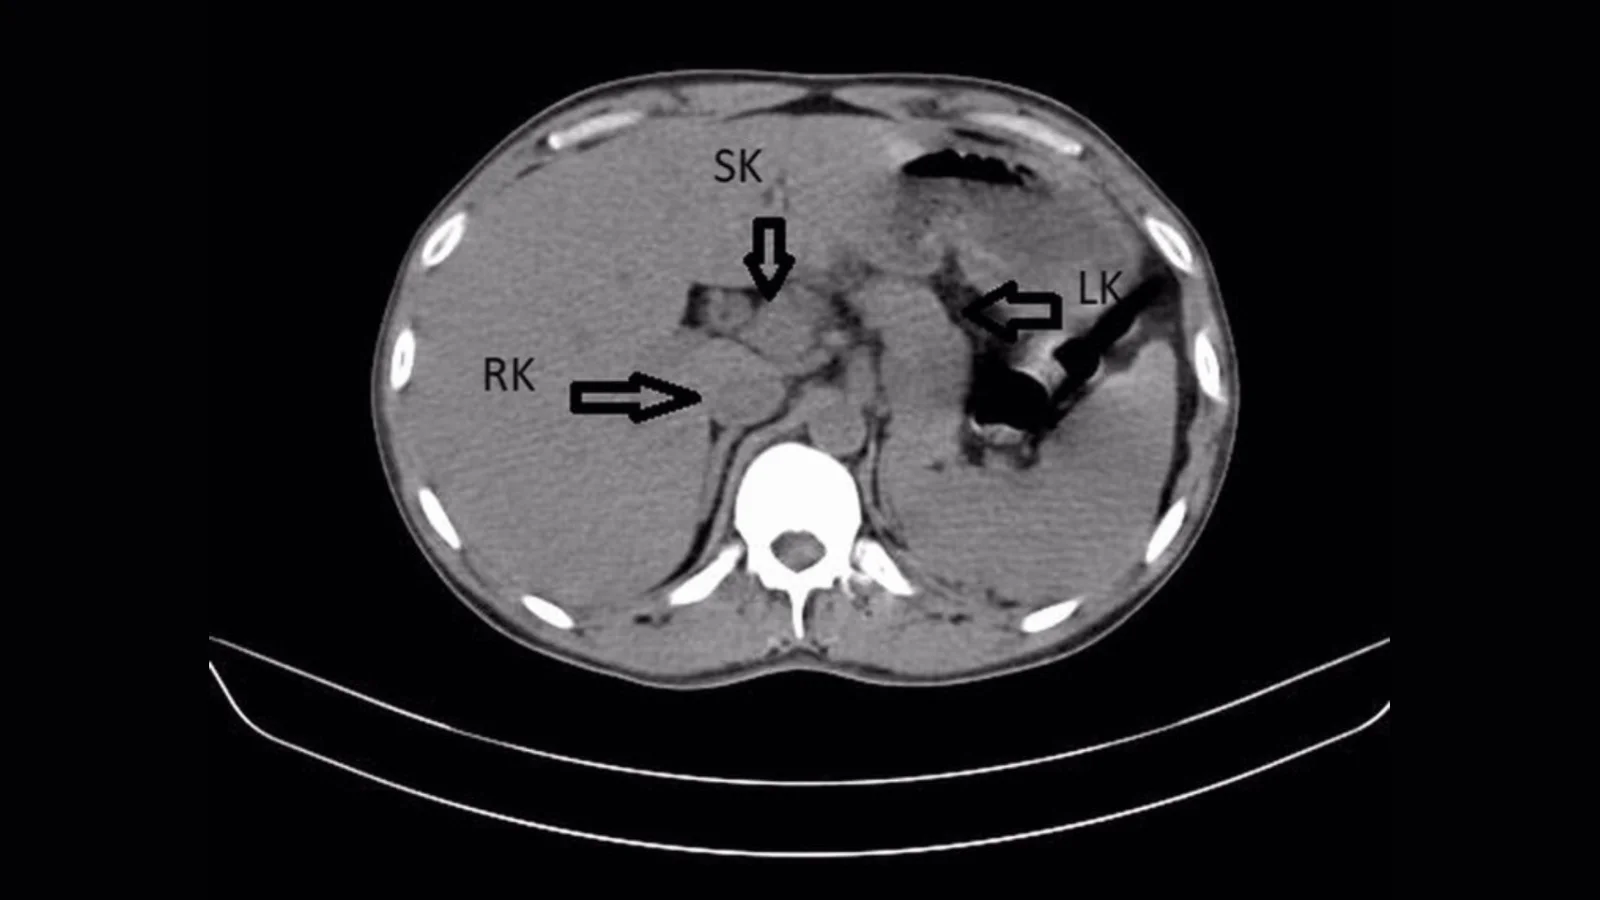

A 31-year-old man in Wardha, India, treated for a urinary tract infection was found to have a rare supernumerary (third) kidney fused to his right kidney on CT imaging. The congenital anomaly can be asymptomatic, but in this case the kidneys were swollen and there were stones in the left ureter. He received a ureteral stent and IV antibiotics; after 48 hours he improved and was discharged with follow-up. Supernumerary kidneys are exceedingly rare (fewer than 100 cases per year worldwide), and a fused horseshoe configuration is even more unusual.